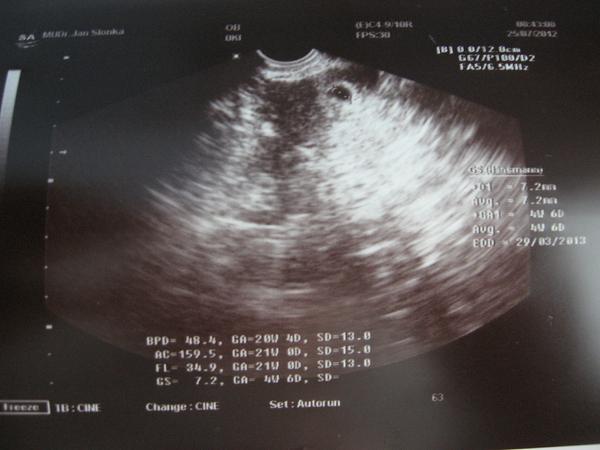

Tak děvčata přidávám dnešní zážitek z UZ...Velký UZ na genetice na kontrolu, normální člověk se těší (což i já) ale aby odcházel s pláčem a to ne proto, že miminko je nemocné, ale proto, že doktorka je sprominutím K.... tak to je na mě moc...Ano jsem baculka a tak vizualizace do pidi detajlů je horší, ale aby mě mlátila do břicha a UZ prováděla obouručně zapřená celou vahou těla do mého bříška je šílený..Trvalo to hodinu a půl a výsledek je ten, že mám modřinu jak od dvou tenisáků na bříšku, šílené bolesti u dýchání a sebemenším pohybu a že mám tendenci volat rychlou...A to jen proto aby zjistila jestli srdeční aorta má 2 nebo 3mm upřímně pro mě bylo hlavní že má všechno tak jak má a tenhle detajl by oželila i má Dr....Něco pozitivního sem: V bříšku je 100% Verunka, před UZ a snad i nyní po něm 100% zdravá a 25cm veliká slečna...Doufám že žádnou z vás tenhle přístup nepotká a to podotýkám, nikdy sem na břiše neměla přemíru tuku - muj problém jsou stehna :(